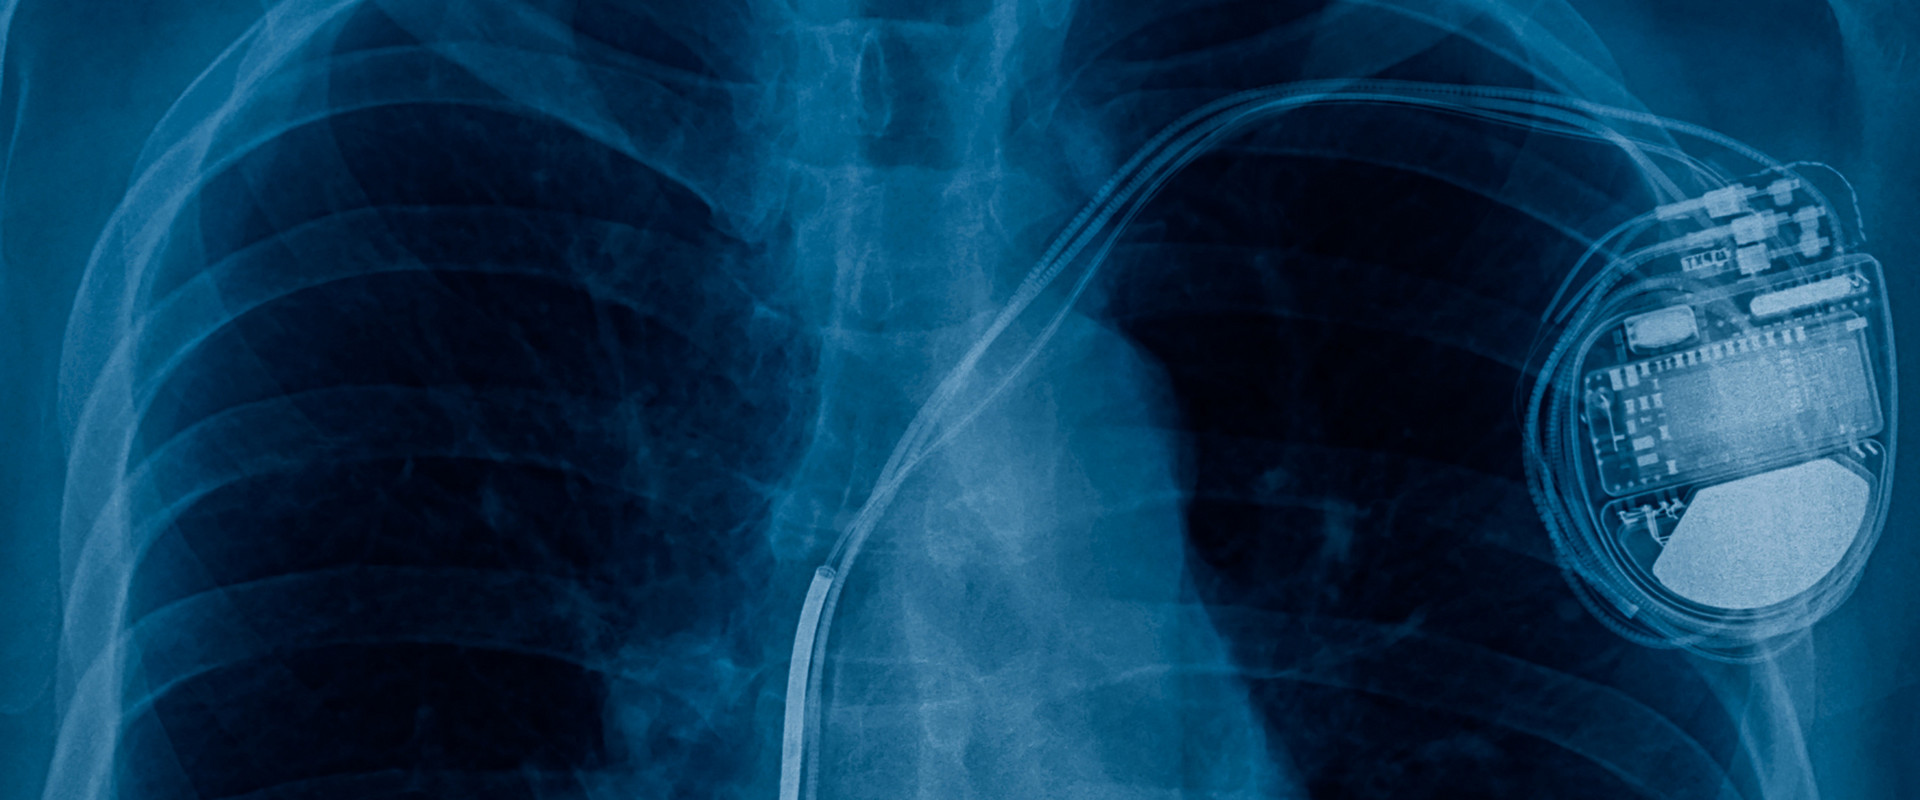

HERZSCHRITTACHER

Bei jedem dritten Betroffenen pumpen die beiden Herzkammern nicht mehr synchron (gleichzeitig). Systeme zur kardialen Resynchronisation, von Kardiologen als CRT-Systeme bezeichnet, sind Schrittmachersysteme, die mit einer dritten Elektrode ausgestattet sind. Das Gerät umfasst somit sämtliche Funktionen eines normalen Herzschrittmachers, bietet ergänzend jedoch die Möglichkeit, die rechte und linke Herzkammer synchron zu stimulieren.

Ziel einer kardialen Resynchronisationstherapie ist, die Kontraktion der beiden Herzkammern aufeinander abzustimmen, zu resynchronisieren. Dies führt bei einer Herzschwäche zu einer verbesserten Überlebenschance und zu einer Steigerung der Leistungsfähigkeit. CRT-Systeme werden bevorzugt Patienten empfohlen, bei denen mittels EKG ein sogenannter Linksschenkelblock festgestellt wurde. Bei Herzschwäche-Patienten mit einem zu langsamen Herzschlag, von Kardiologen Bradykardie genannt, kann die Implantation eines konventionellen Herzschrittmachers eine erfolgreiche Therapiemethode sein.